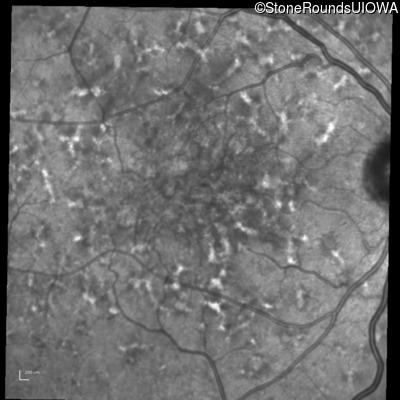

Pattern Dystrophy (IIC)

Age at visit: 49 years

This 49 year old man was first told he had a fundus abnormality on a routine eye exam at age 34. Ten years later he noticed some distortion just superior to fixation.

Pattern Dystrophy PRPH2 Gln239Stop CAG>TAG   AD